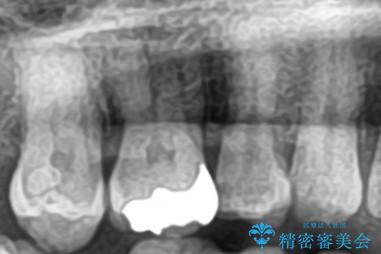

セラミックインレー 虫歯の治療

- 定期健診で虫歯が見つかり、治療が必要となりました。材料の物性を説明し、セラミックインレーでの治療となりました。

接着操作時にはラバーダム防湿を行いました。